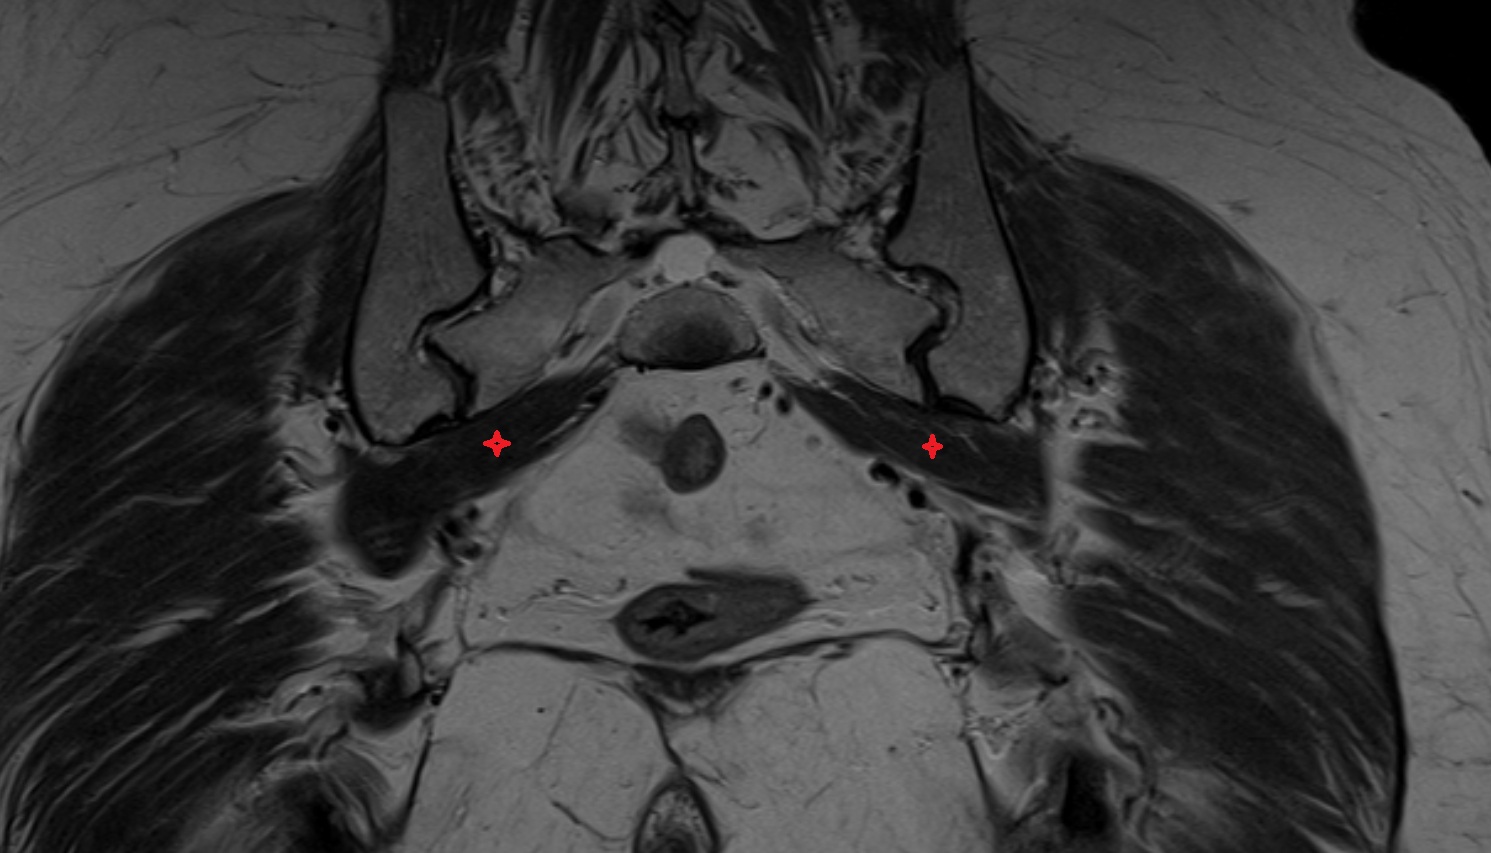

- Piriformis muscle

- Obturator internus muscle